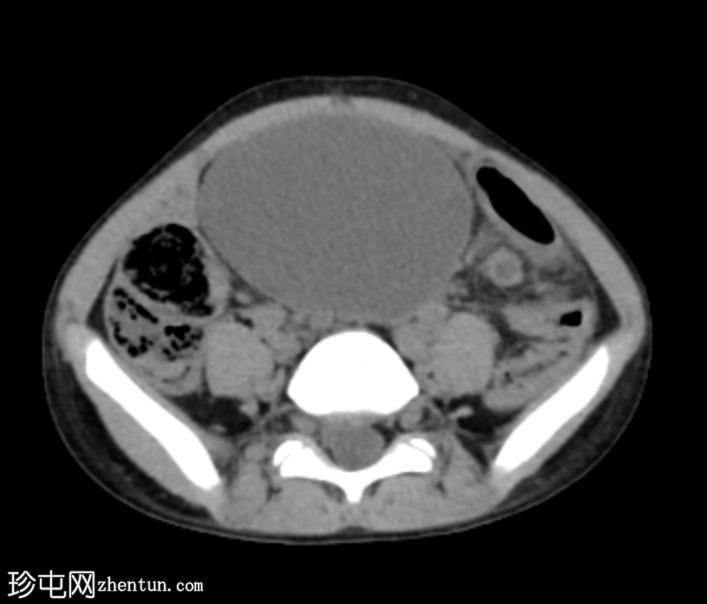

矢状位增强扫描(门静脉期)

阑尾过长,跨越中线向左侧延伸。阑尾呈扩张状态,充满液体(8mm),管壁增厚并强化,近端可见多发性穿孔。阑尾周围脂肪间隙模糊,可见液体密度影和管腔外气体。未见脓肿。